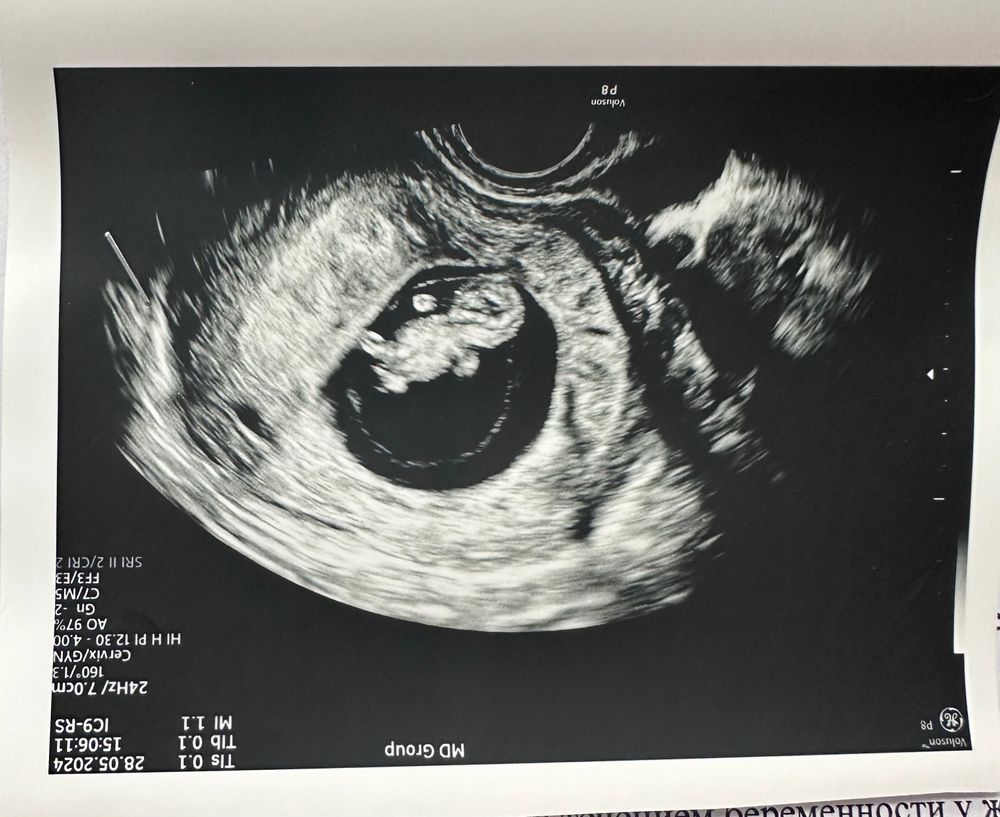

10-ая неделя,полет нормальный

Всё о нашей беременностиУЗИ порадовало,тк человек растет себе потихоньку,копошится там и не дала сфоткать ее в профиль))) а в анфас РЕ назвала ее медвежонком и трудно поспорить 😂 голова круглая,живот толстый,по бокам ручки-ножки. Во время УЗИ доктор на экране показала,как она шевелила пальцами на ручках. Это выглядело максимально забавно.

Как обычно никаких параметров в УЗИ не внесли,но я запомнила,что КТР 24,1